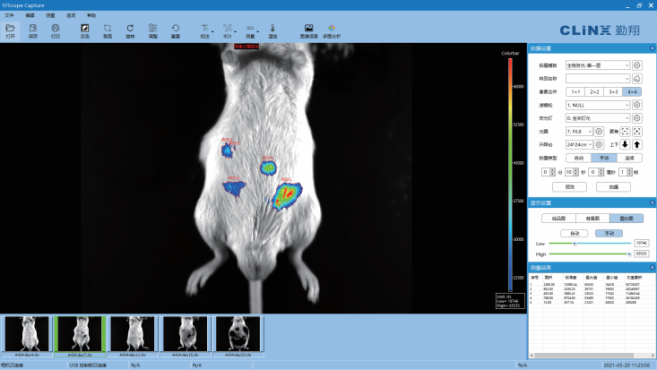

(小动物活体成像系统软件界面)

①实时监控:可通过预览功能在软件窗口对样品进行实时检测;

②图像连续采集:通过软件设置曝光时间和连续帧数,连续拍摄一组图像而不会错过短暂荧光或生物发光信号,拍摄结果自动保存;

③图像编辑:具有图像的旋转、裁剪、反色等处理功能,进行图像优化处理;

④伪彩叠加:调色板色彩丰富,让用户可根据自己的使用习惯叠加伪彩,从而大大增加肉眼对灰阶图像的视觉分辨能力;

⑤软件算法强大:可对ROI区域进行分析,并具有图像批处理功能;

⑥预置拍摄参数:自动保存及读取拍摄参数,避免拍摄时重复设置参数;

⑦ 模块控制功能:可通过电脑实现对系统每个模块的控制,包括对升降台、荧光系统和滤镜轮的控制;

⑧支持以动态视频形式输出实验结果。